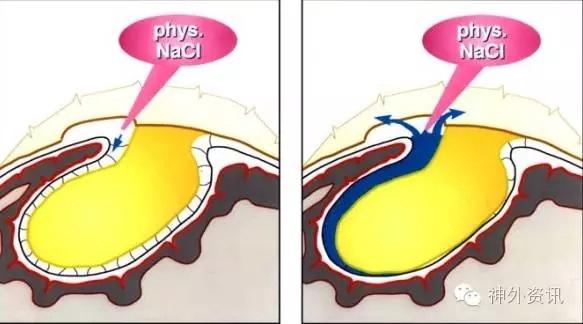

水分离技术(Water Dissection Technique)最早由匈牙利神经外科医师Toth在1987年提出,但却未得到应有的认可,直到近年来才得到广泛使用。水分离技术的方法其实很简单(见图1、图2、图3),手持20ml或50ml注射器+钝针头,对需要分离的界面不断冲洗和体温一致的生理盐水,延伸扩展裂隙空间,以进一步辨别分离。

图2. 水分离技术。

作为神经外科医师,最常遇到的就是可分离界面(Cleavage Planes),它需要术者耐心的寻找,轻柔的打开、扩大、分离,以免损伤正常的脑组织。这样的界面一般有两种:

解剖存在的自然界面但粘连较紧甚至为潜在界面,例如分离小脑扁桃体与延髓,进入四脑室;分离侧裂以夹闭大脑中动脉瘤或者切除岛叶肿瘤,分离纵裂以切除镰旁肿瘤、夹闭胼周、胼缘动脉瘤、切除侧脑室三脑室內肿瘤,详见笔者前文《经纵裂侧方胼胝体入路,三脑室內中前部占位的首选?》。

膨胀性生长压迫脑组织的脑外病变,例如脑膜瘤、大型动脉瘤,其他一些非神经源性肿瘤。此类病变大多呈非侵袭性生长,多存在蛛网膜间隙,均可利用水分离技术来扩大界面。

水分离技术也有其并发症,常会出现错层现象,即应有界面未打开,同时又破坏脑组织;造成此现象的原因常常是因为高张力的存在,例如分离侧裂时,如脑压较高,可通过打开颅底池、切开终板或者Paine’s点穿刺侧脑室来释放脑脊液后,再水分离侧裂;而分离肿瘤时,亦是肿瘤的內减容和水分离肿瘤界面交替进行,以避免错层现象的发生。